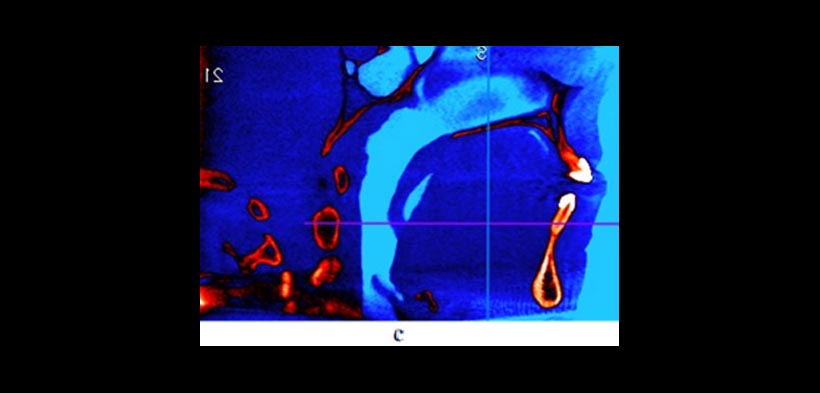

Figura 1. Relación espacial dentoalveolar (A) Una radiografía panorámica ofrece limitado información sobre la localización exacta de los caninos y su relación con las raíces de los incisivos laterales. En contraste, (b) imagen oclusal, (c) frontal y (d) una vista superior de la reconstrucción volumétrica en 3d, muestran la presencia de la reabsorción radicular en ambos incisivos laterales. Estas imágenes también proporcionan importantes Información para el ortodoncsta o cirujano sobre el mejor abordaje.

Figura 2. Uso de la CBCT en el diagnóstico y la planificación del tratamiento de los dientes transpuestos. Un caso que demuestra raíces transpuestas de los caninos superiores y los primeros premolares en la que la CBCT revela que la raíz canina está a vestibular de la raíz premolar. (a) Reconstrucción tridimensional y (b, c) imágenes transversales y la ubicación de la raíz. Todos estos cortes tomográficos pueden ayudar al clínico a optimizar la planificación del tratamiento.

Figura 3. La CBCT ofrece información sobre las condiciones de frontera que no son discernibles a partir de radiografías de rutina o durante el examen clínico, que pueden tener un impacto sobre las opciones de tratamiento. (a) Pre-tratamiento vista coronal que muestra la inclinación lingual (flechas) de los premolares maxilares y la proximidad de sus raíces bucales al margen de la cortical alveolar (puntas de flecha). (b) Post-tratamiento vista coronal que demuestra que las limitaciones ofrecidas por las condiciones de contorno relaciones hueso de la raíz se han abordado mediante torsión lingual de las raíces. (c) vista sagital y (d) vista transversal de la una CBCT de un individuo con limitaciones severas en las condiciones de contorno donde hay ausencia de corticales óseas. El tratamiento de ortodoncia estaría contraindicado en este caso.